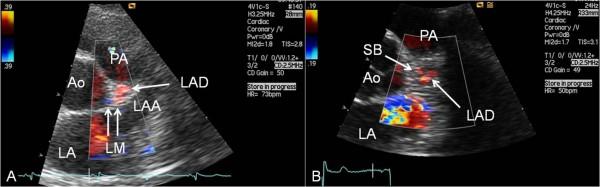

Transthoracic echocardiography (TTE) may be used for direct inspection of various parts of the main coronary arteries for detection of coronary stenoses and occlusions. We aimed to assess the feasibility of TTE to visualise the complete segments of the left main (LM), left descending (LAD), circumflex (Cx) and right (RCA) coronary arteries.

One hundred and eleven patients scheduled for diagnostic coronary angiography because of chest pain or acute coronary syndrome had a TTE study to map the passage of the main coronary arteries. LAD, Cx and RCA were each divided into proximal, middle and distal segments. If any part of the individual segment of a coronary artery with antegrade blood flow was not visualised, the segment was labeled as not satisfactorily seen.

经胸超声心动图(TTE)可用于直接检查主要冠状动脉的各个部分,以检测冠状动脉狭窄和闭塞情况。我们旨在评估TTE对左主干(LM)、左前降支(LAD)、回旋支(Cx)和右冠状动脉(RCA)完整节段进行成像的可行性。

111例因胸痛或急性冠状动脉综合征而计划进行诊断性冠状动脉造影的患者接受了TTE检查,以描绘主要冠状动脉的走行。LAD、Cx和RCA均分为近端、中段和远端节段。如果冠状动脉某单个节段有正向血流但其中任何部分未被显示,则该节段标记为显示不满意。